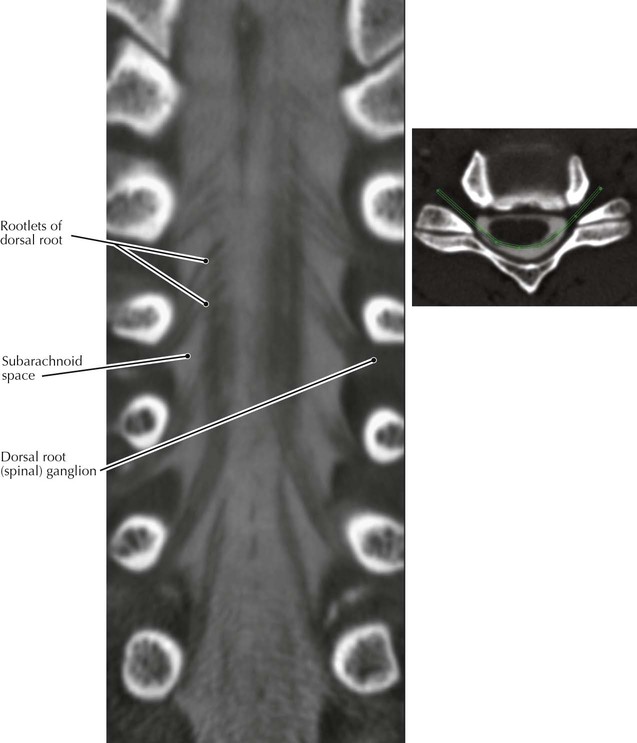

• In this CT image the rootlets of the dorsal roots are represented by the delicate black inclined lines; the gray material represents opacified (contrast-enhanced) cerebrospinal fluid (CSF) within the subarachnoid space. The CSF was opacified by an intradural injection of iodinated contrast material that was injected with a very fine needle during a simple outpatient procedure.

• For patients who cannot undergo MRI—for example, those with a pacemaker—CT myelography is an alternative imaging procedure that is capable of showing very delicate anatomy (e.g., spinal nerve rootlets).